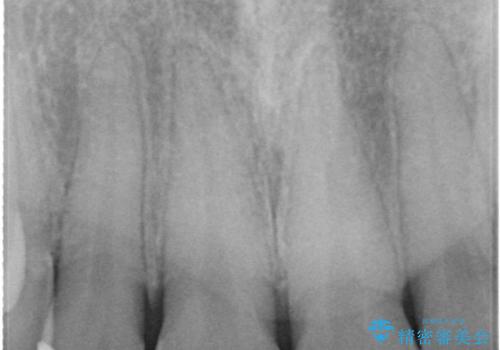

- 前歯の歯並びが気になるとのことで来院されました。

右上の1番目の歯が内側に入り込んでしまっており、その歯がの先端がすり減ってしまっていました。

インビザラインによる矯正治療で前歯の歯並びを改善し、セラミッククラウン装着により歯の形態の回復をする計画としました。